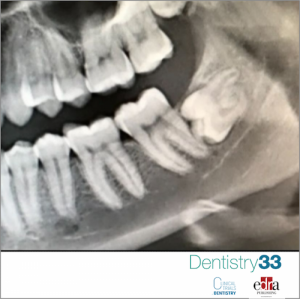

The surgical extraction of the third molar includes rising a flap, ostectomy and suturing. These procedures could cause swelling, trismus and moderate to severe pain. In oral surgery pain control is a key factor for reducing fear and anxiety in patients. Painmanagement is usually based on different analgesic medications. Tramadol is a centrally acting weak opioid analgesic clinically effective in treating moderate to moderately severe pain. tramadol is an atypical opioid and when administered locally, it has both analgesic and anesthetic properties.

This study aims to evaluate the effectiveness of submucosal application of tramadol against acute postoperative facial pain, following the extraction of impacted third molar.

60 patients underwent impacted third molar surgery under local anaesthesia and then were randomly divided into two groups according to a prospective, double-blind, placebo-controlled study design.

-group T: received submucosally 1 mg/kg tramadol

-group S: received submucosally 2-mL saline

Pain after extraction was evaluated using a visual analogue scale (VAS) 0.5, 1, 2, 4, 6, 12, 24, and 48 h postoperatively.

Group S registered VAS scores significantly higher compared to group T at 1, 2, 4, 6 and 12 h after molar extraction, but no significant differences at 24 and 48 h (p > 0.05). As regard the first analgesic dose taken, group T swallowed it significantly later compared to the control group (p = 0.0001). There were no significant differences between the two groups in side-effects (nausea, vomiting, burning, and dizziness).

In modern time, all procedures in oral surgery should be painless and management of postoperative pain needs to be adequate. This study demonstrated the effectiveness of submucosal application of tramadol in reducing acute post-operative facial pain after third molar surgery.